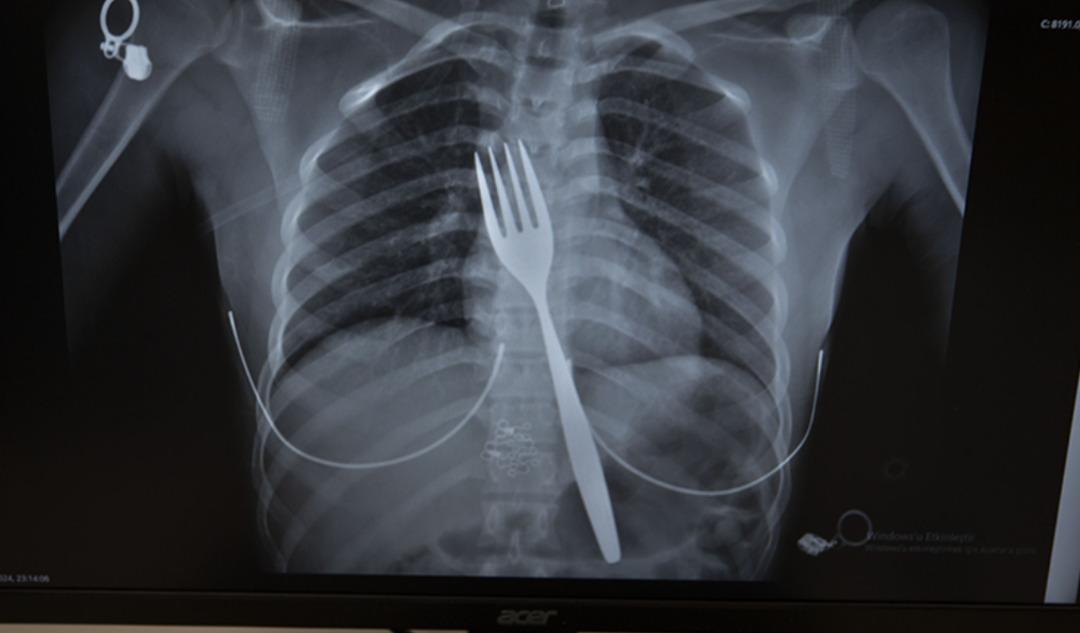

Söke'de ikamet eden yabancı uyruklu EE (18), çatal yutma şikayetiyle ambulansla Aydın Adnan Menderes Üniversitesi Hastanesi'ne (ADÜ) götürüldü. Burada röntgeni çekilen hastanın yemek borusunda 18 santimetrelik çatal olduğu belirlendi.

Uzmanlar endoskopi yaparak çatalı ağızdan çıkarmaya çalıştı. Ancak yemeğe ve nefes borusuna zarar verme ihtimali nedeniyle midenin kesilip çatalın çıkarılmasına karar verildi.

ADÜ Tıp Fakültesi Göğüs Cerrahisi Anabilim Dalı Öğretim Üyesi Dr. Salih Çokpınar ve Genel Cerrahi Anabilim Dalı Dr. Öğretim Üyesi Akay Edizsoy'un koordine ettiği operasyonda midede kesi yapılarak çatal çıkarıldı.

Edizsoy, vakayı ilk duyduğunda şaşırdığını belirterek, şöyle konuştu: “Büyük bir çatalın tamamen yutulması sonucu oluşan bu vakayı ilk duyduğumda doğru olmadığını düşünmüştüm. Hasta 18 yaşında ve 18 yaşındaydı. Yabancı uyruklu. Türkçesi biraz zayıf olduğu için bir yanlış anlaşılma olabileceğini düşündük ama hastayı çektiğimizde aslında çatal yutuyordu.” “Yemek borusunda olduğunu gördük.” dedi.

“Bu yüzden çok endişelendik. Ancak endoskopide ciddi bir lezyonun olmadığını gördük. Oldukça büyük olduğundan ve endoskopik aletlere uygun olmadığından endoskopiyle çıkarılamadı. Büyük bir masa çatalı olduğu için kendine ait. ağırlıktır. Bir çivi gibidir, bir iğne gibidir. “Tutulamaz ve çıkarılamaz. Bu nedenle karından kesi yaparak mideye ulaşıp midenin içinden çıkarma stratejisi izledik. Bu ameliyatla bu çatalı oradan çıkarmayı başardık.”